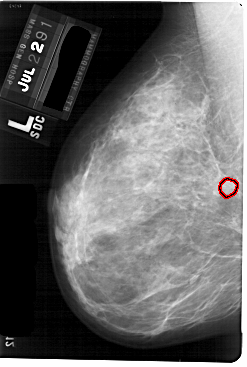

A_1757_1.LEFT_MLO

FILE: A_1757_1.LEFT_MLO.OVERLAY

TOTAL_ABNORMALITIES 1

ABNORMALITY 1

LESION_TYPE MASS SHAPE ROUND MARGINS OBSCURED

ASSESSMENT 3

SUBTLETY 3

PATHOLOGY BENIGN

TOTAL_OUTLINES 1

BOUNDARY